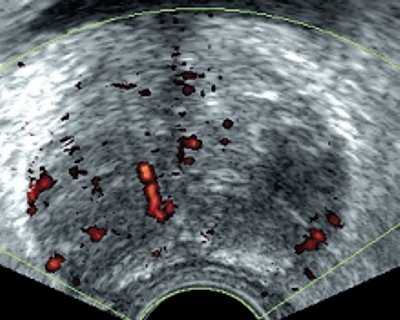

В большинстве случаев (75% больных) опухолевый участок при ТРУЗИ был гипоэхогенным и локализовался в периферической зоне. У одного пациента определялся гипоэхогенный участок, захватывающий периферическую и центральную части. У двух пациентов, используя стандартные методики ТРУЗИ, нельзя было установить границу между нормальной и опухолевой тканью. В нашем исследовании прорастание опухолью стенки мочевого пузыря выявлено у трех пациентов (стадия Т4) (рис.1); прорастание рака предстательной железы в семенные пузырьки определялось у 4 больных (стадия Т3b) (рис.2); капсула прослеживалась на всем протяжении у 11 пациентов с раком предстательной железы (стадия Т2) (рис. 3а); у двух пациентов целостность капсулы была нарушена (стадия Т3а) (рис. 3б). Степень распространения опухоли определяла тактику лечения.

Рис. 1. Тотальное опухолевое поражение предстательной железы на фоне аденомы. Опухоль полностью изоэхогенна ткани аденомы. Поперечный срез предстательной железы.

Рис. 2. Прорастание рака предстательной железы в семенной пузырек. Определяется расширенный, гипоэхогенный семенной пузырек слева. Поперечный срез на уровне семенных пузырьков.

При анализе результатов ТРУЗИ в режиме серой шкалы нельзя было однозначно трактовать фокальные изменения как злокачественные или доброкачественные. Гипоэхогенные участки, расположенные в периферической зоне, дифференцировали с простатитом, а участки в переходной зоне - с узлами доброкачественной гиперплазии предстательной железы. Поэтому во всех случаях в выявленных гипоэхогенных участках исследовали кровоток с помощью энергетического картирования и 3D-реконструкции сосудов. Использование 3D-реконструкции сосудов в режиме энергетического допплеровского картирования позволяет получить более богатую и насыщенную сосудами картину, чем при обычном двухмерном исследовании, и легче выявить зоны асимметрии васкуляризации. У всех пациентов при раке предстательной железы определялись патологически измененные сосуды в зоне гипоэхогенных участков опухоли (рис.4), которые в отличие от неизмененных сосудов были извиты, прерывисты, имели различный калибр, хаотично располагались в зоне опухоли. Степень васкуляризации опухоли была различной - от гиповаскулярной до гиперваскулярной.

Рис. 4. Патологические изменения в сосудах при раке предстательной железы, асимметрия васкуляризации долей в режиме энергетического картирования и с применением 3D-реконструкции.

В наших наблюдениях у 20 больных раком предстательной железы при двухмерном энергетическом картировании усиление васкуляризации гипоэхогенного участка отчетливо диагностировалось у 6 пациентов, а при 3D-реконструкции сосудов в режиме энергетического картирования у 10. У всех пациентов с раком предстательной железы при 3D-ангиографии определялась асимметрия васкуляризации.